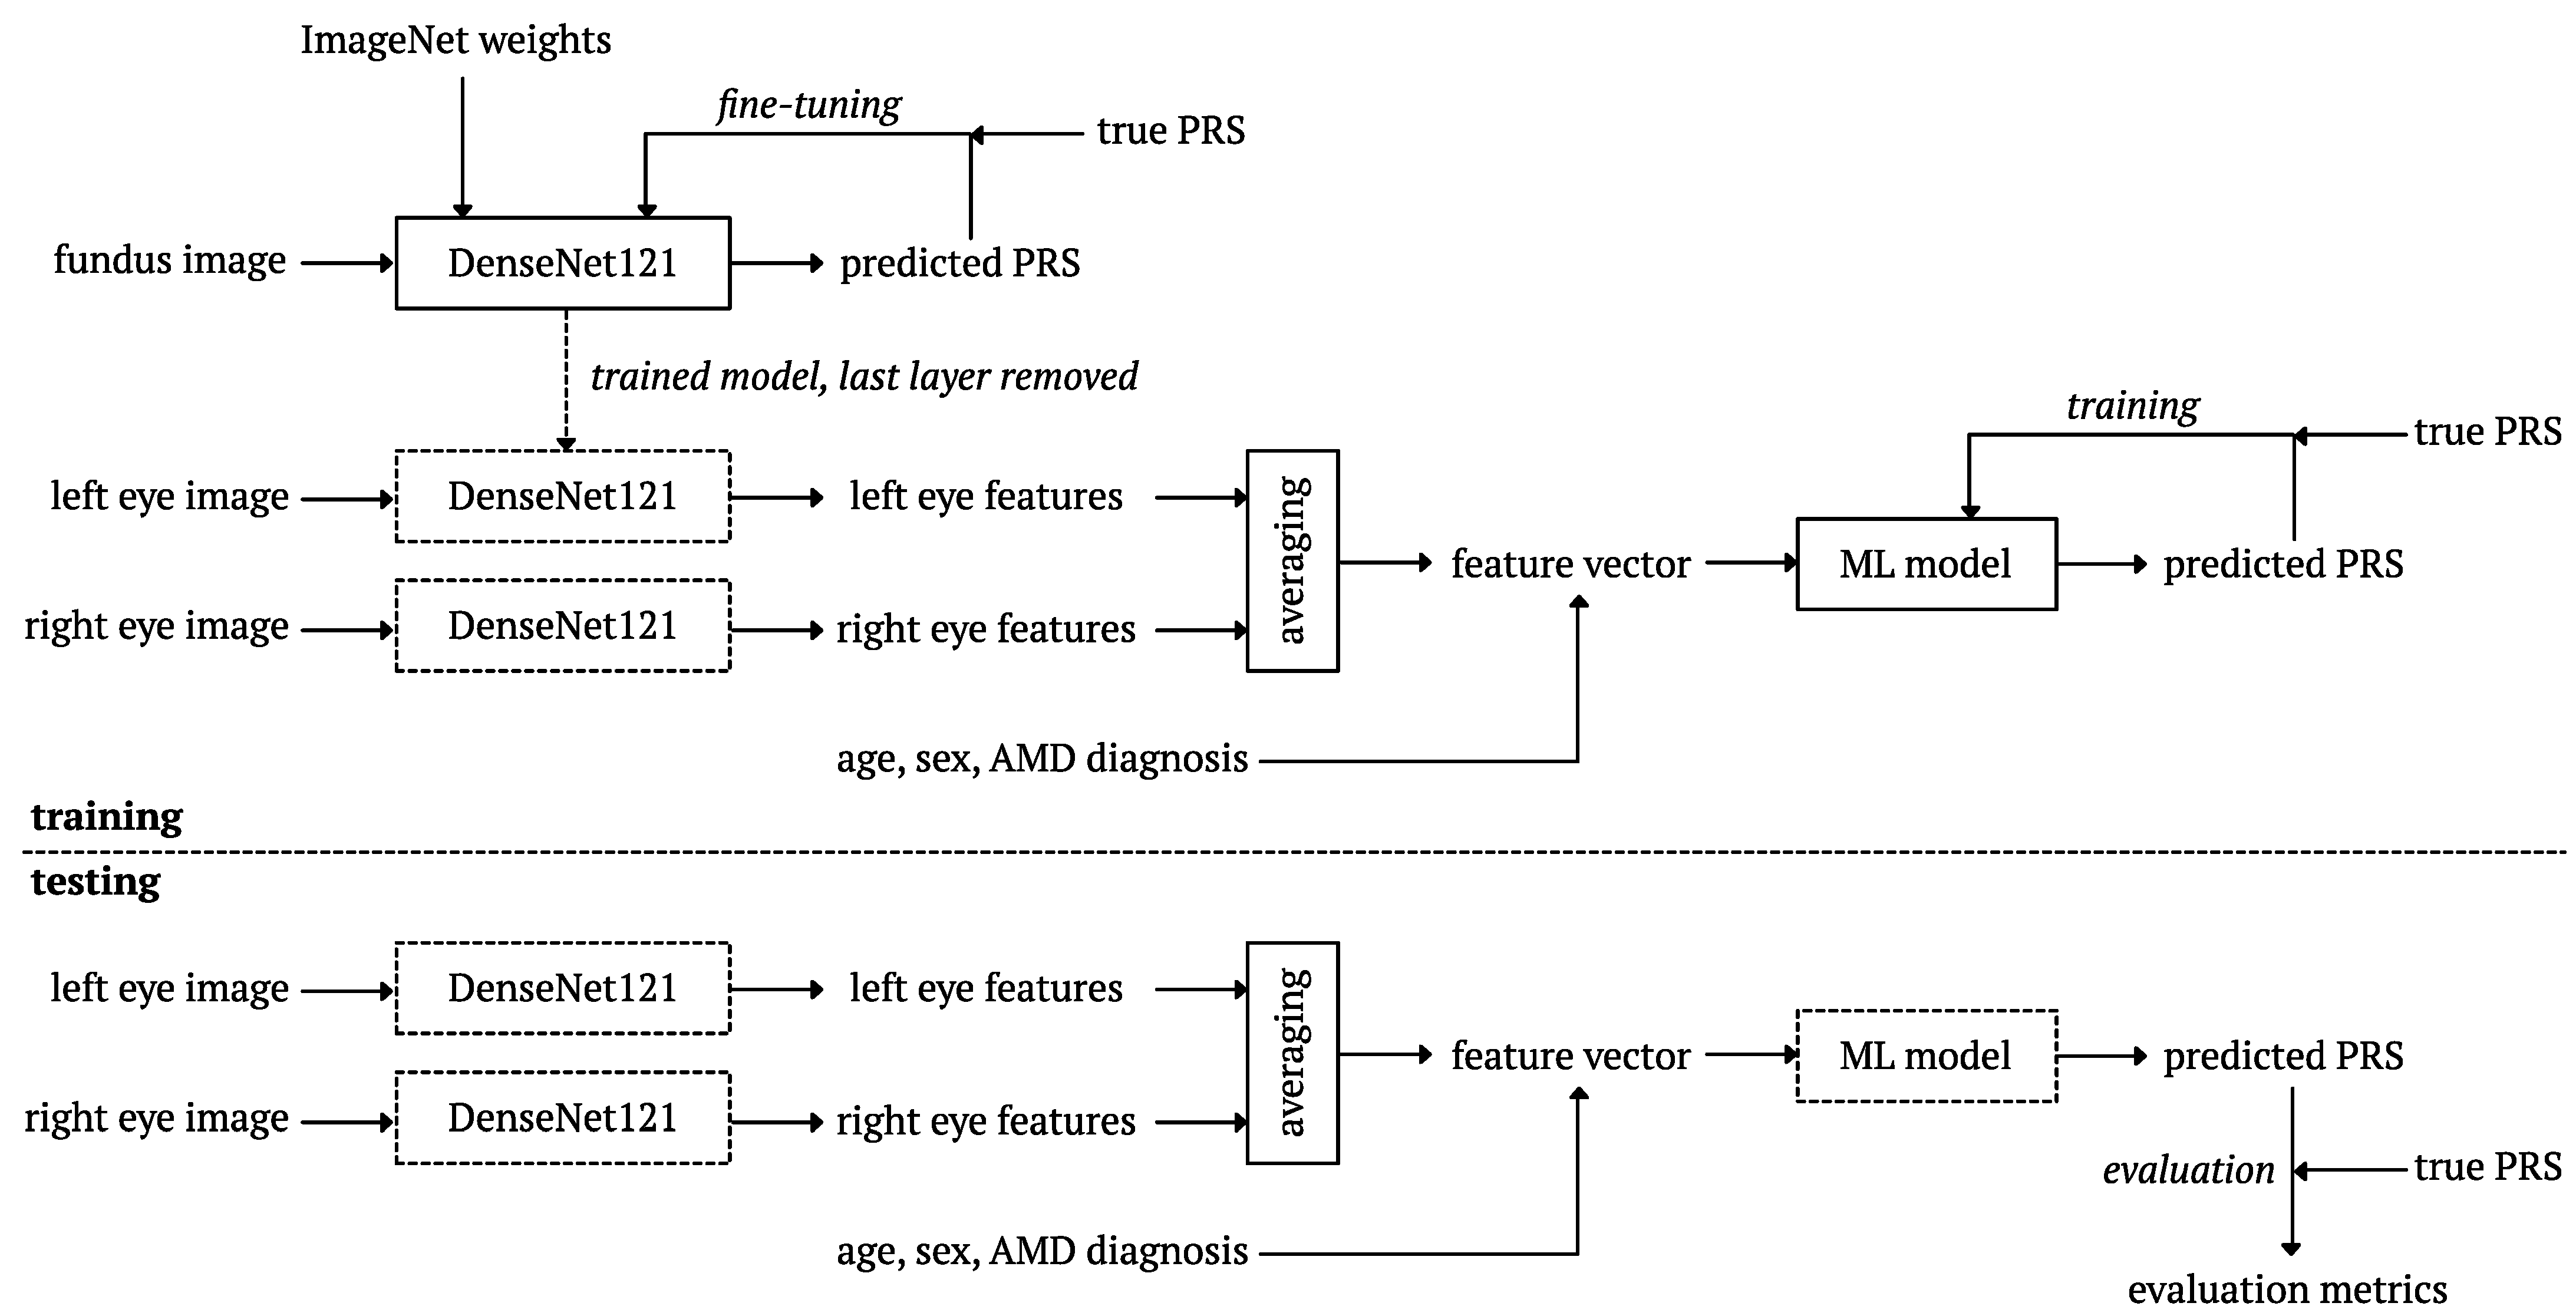

2.7. Deep Learning